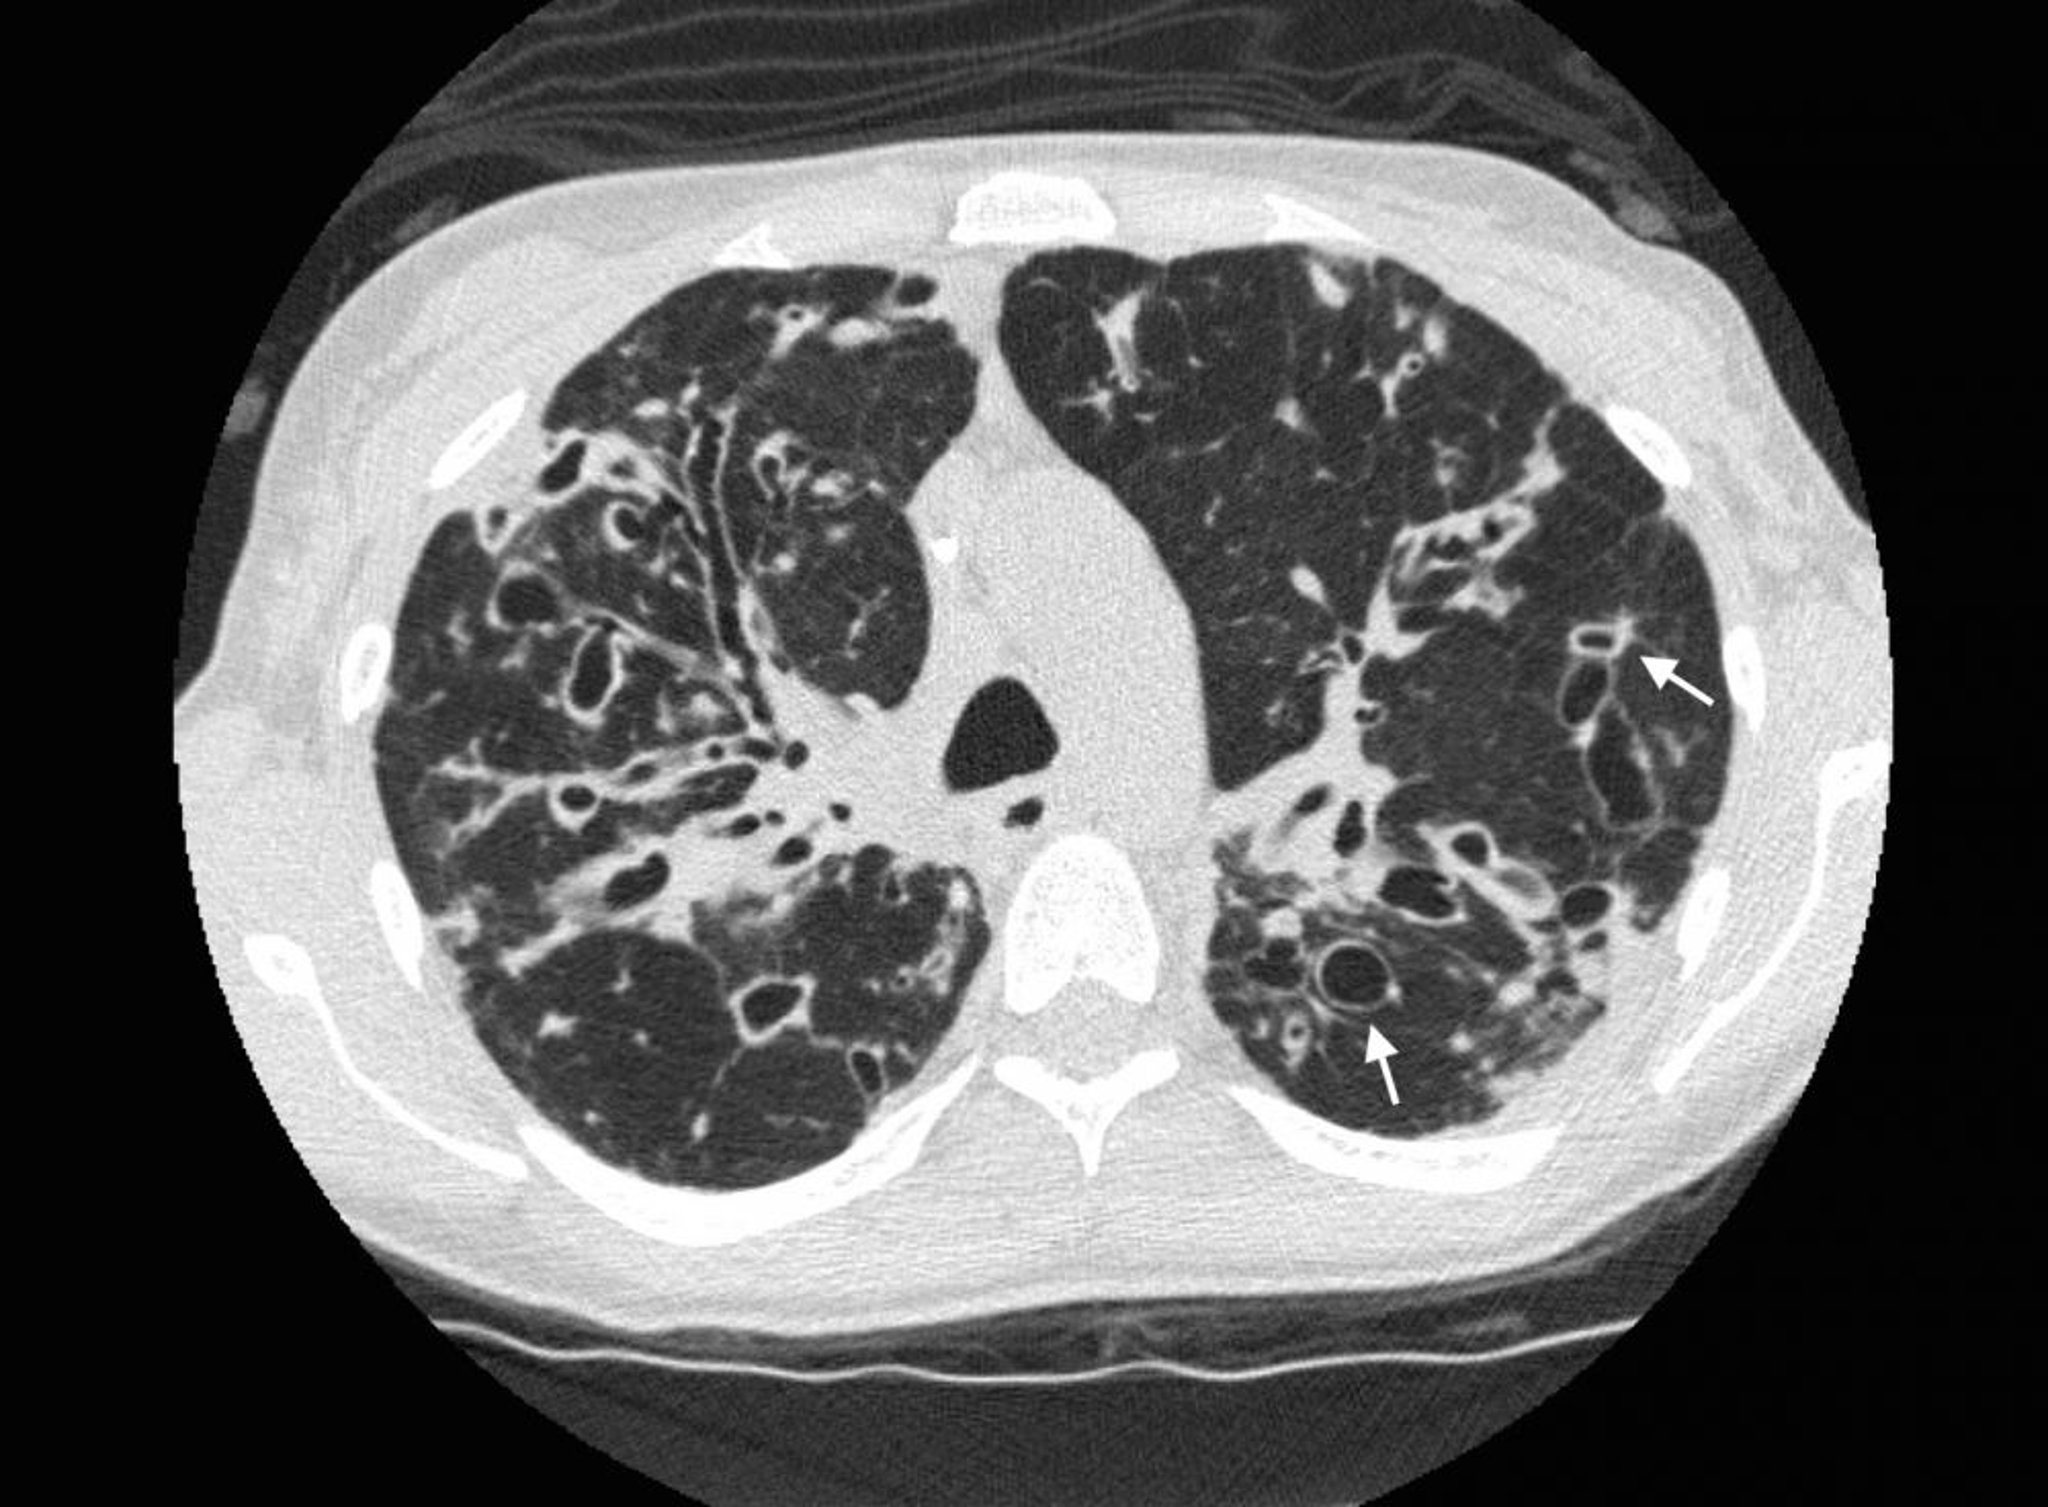

Bronquiectasias (tomografía computarizada)

Una TC de tórax en un paciente con fibrosis quística muestra bronquiectasias graves en los campos pulmonares superiores con vías aéreas dilatadas y cambios quísticos. Las flechas muestran el signo del anillo de sello, donde una vía aérea dilatada (el anillo) está adyacente a una arteria más pequeña (la parte superior del anillo). Normalmente, las vías aéreas son del mismo tamaño o más pequeñas que las arterias adyacentes.

Photo courtesy of Başak Çoruh, MD.